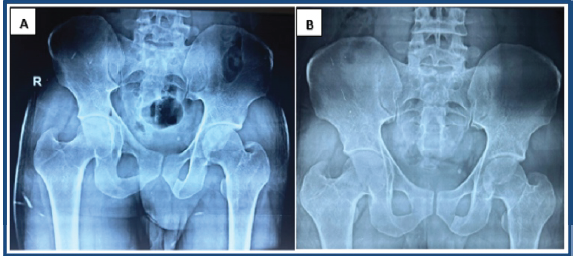

Post-surgery, X–rays and CT scans were done, which showed concentric, congruent and reduced hip without any incarcerated fracture fragment in the left hip joint with stable and minimally displaced fracture of the posterior wall of the acetabulum (Fig. 3). At 6 weeks, radiographs showed a stable and congruous left hip with a uniting fracture posterior wall of the acetabulum (Fig. 4). Early range of motion exercises initiated by the 2nd week, progression to partial and full weight-bearing based on pain and imaging. At 8 weeks, the patient has good functional and radiological outcomes (Fig. 5).

Figure 4: Follow-up X-ray after 4 weeks (a) and after 8 weeks (b) showing congruous left hip joint and uniting fracture of the posterior wall of the acetabulum.